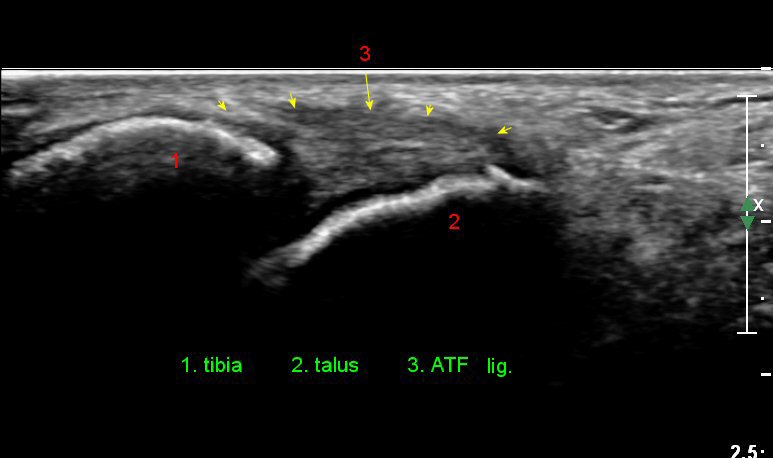

Àü¹æ °æ°ñºñ°ñÀδë Á¾´Ü¸é°Ë»ç¿¡¼­ ƯÀÌ ¼Ò°ßÀ» º¸ÀÌÁö ¾Ê´Â´Ù(»çÁø 3).

Àü°ÅºñÀδë Á¾´Ü¸é°Ë»ç¿¡¼­ ¾È´ë ºñ°ñ ºÎÂøºÎÀÇ Àú¿¡ÄÚ ºÎÁ¾°ú ºÎºÐÆÄ¿­ÀÌ °üÂûµÈ´Ù(»çÁø 4).